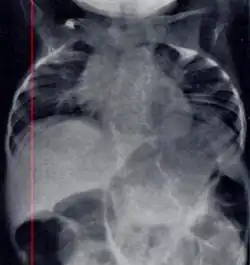

| Radiograph depicting typical skeletal features of Jarcho-Levin syndrome, subtype spondylothoracic dysplasia. Note fanlike configuration of the ribs, with extensive posterior fusion, along with multiple vertebral segmentation defects. | |

Spondylothoracic dysplasia

Spondylothoracic dysplasia, or STD, has been repeatedly described as an autosomal recessively inherited condition that results in a characteristic fan-like configuration of the ribs with minimal intrinsic rib anomalies. Infants born with this condition typically died early in life due to recurrent respiratory infections and pneumonia due to their restricted thorax.[3][4][5] Recently, a report[6] has documented that actual mortality associated with STD is only about 50%, with many survivors leading healthy, independent lives.

In contrast to STD, the subtype spondylocostal dysostosis, or SCD features intrinsic rib anomalies, in addition to vertebral anomalies. Intrinsic rib anomalies include defects such as bifurcation, broadening and fusion that are not directly related to the vertebral anomalies (such as in STD, where extensive posterior rib fusion occurs due to segmentation defects and extreme shortening of the thoracic vertebral column).[6] In both subtypes, the pulmonary restriction may result in pulmonary hypertension, and have other potential cardiac implications.[7]